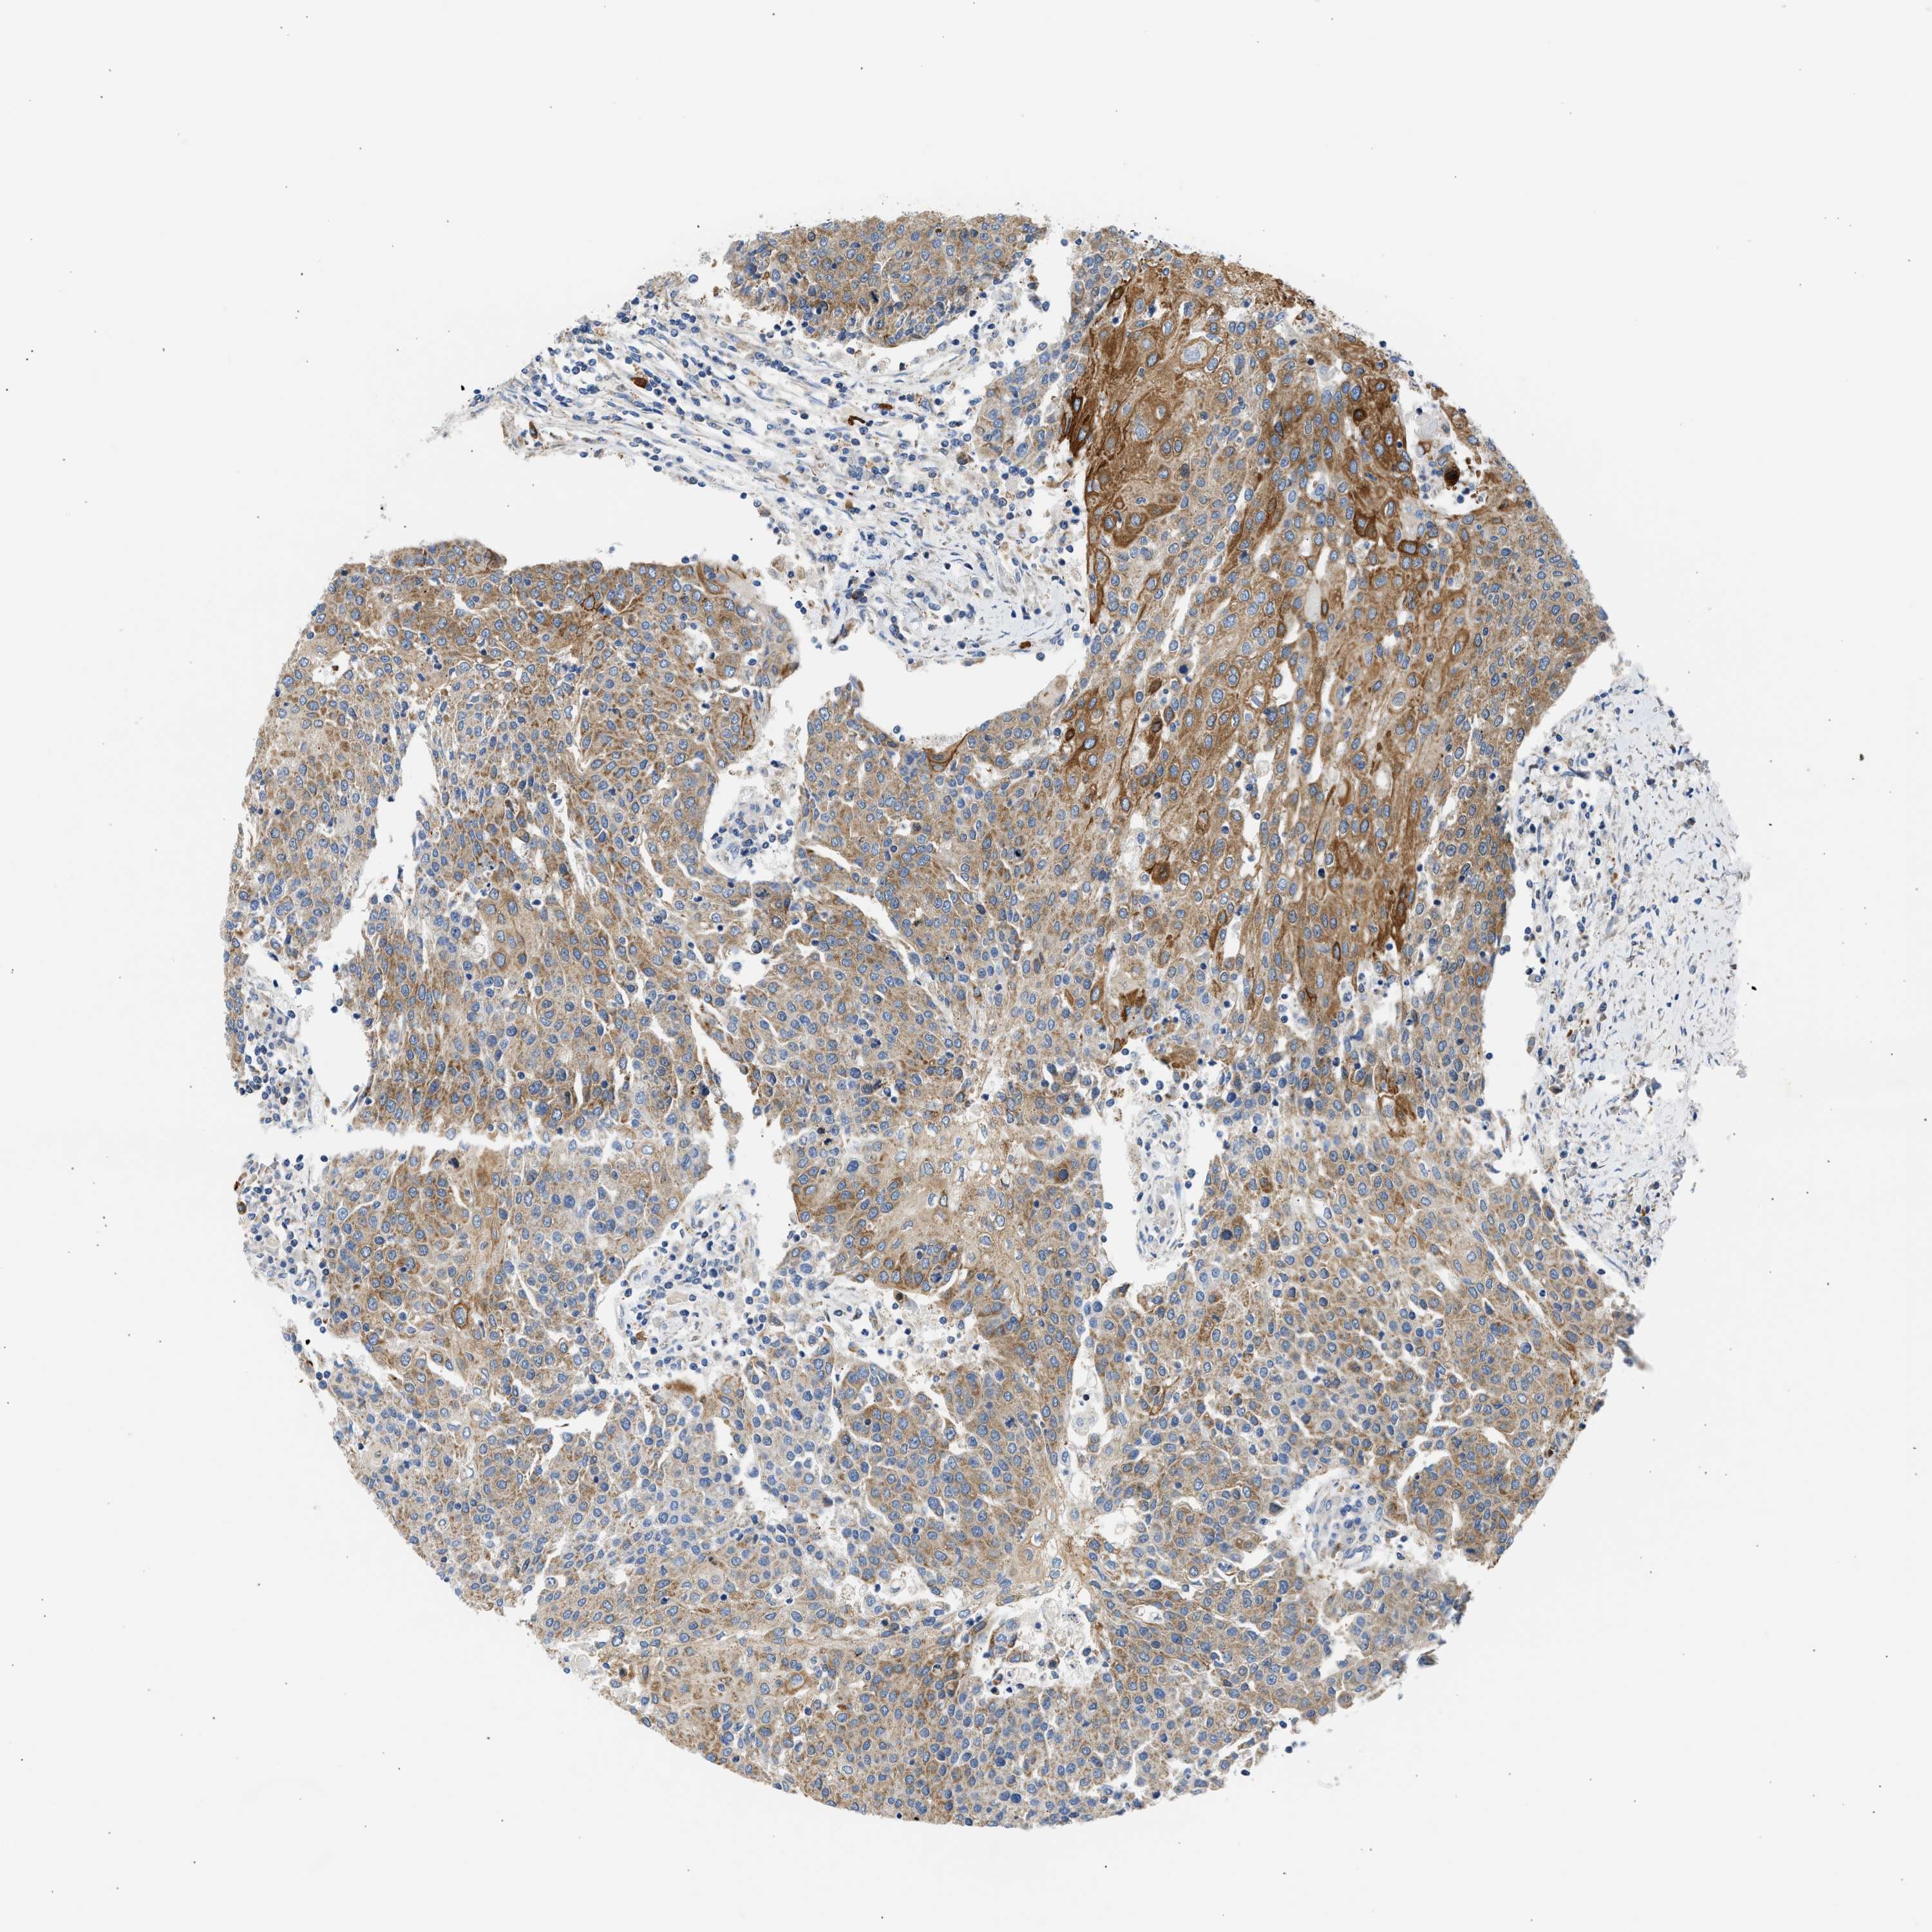

UROTHELIAL CANCER - Protein expressioni

A mouse-over function shows sample information and annotation data. Click on an image to view it in a full screen mode. Samples can be filtered based on level of antibody staining by selecting one or several of the following categories: high, medium, low and not detected. The assay and annotation is described here.

Note that samples used for immunohistochemistry by the Human Protein Atlas do not correspond to samples in the TCGA dataset.

Antibody stainingi

Antibody staining in the annotated cell types in the current human tissue is reported as not detected, low, medium, or high, based on conventional immunohistochemistry profiling in selected tissues. This score is based on the combination of the staining intensity and fraction of stained cells.

Each image is clickable and will lead to virtual microscopy that enables deeper exploration of all samples and also displays staining intensity scores, fraction scores and subcellular localization as well as patient and tissue information for each sample.

Antibody HPA017389

Antibody HPA063713

Staining

High

Medium

Low

Not detected

Intensity

Strong

Moderate

Weak

Negative

Quantity

>75%

75%-25%

<25%

None

Location

Nuclear

Cytoplasmic/membranous

Cytoplasmic/membranous,nuclear

Urothelial carcinoma, Low grade

Urothelial carcinoma, High grade

Urothelial carcinoma, NOS